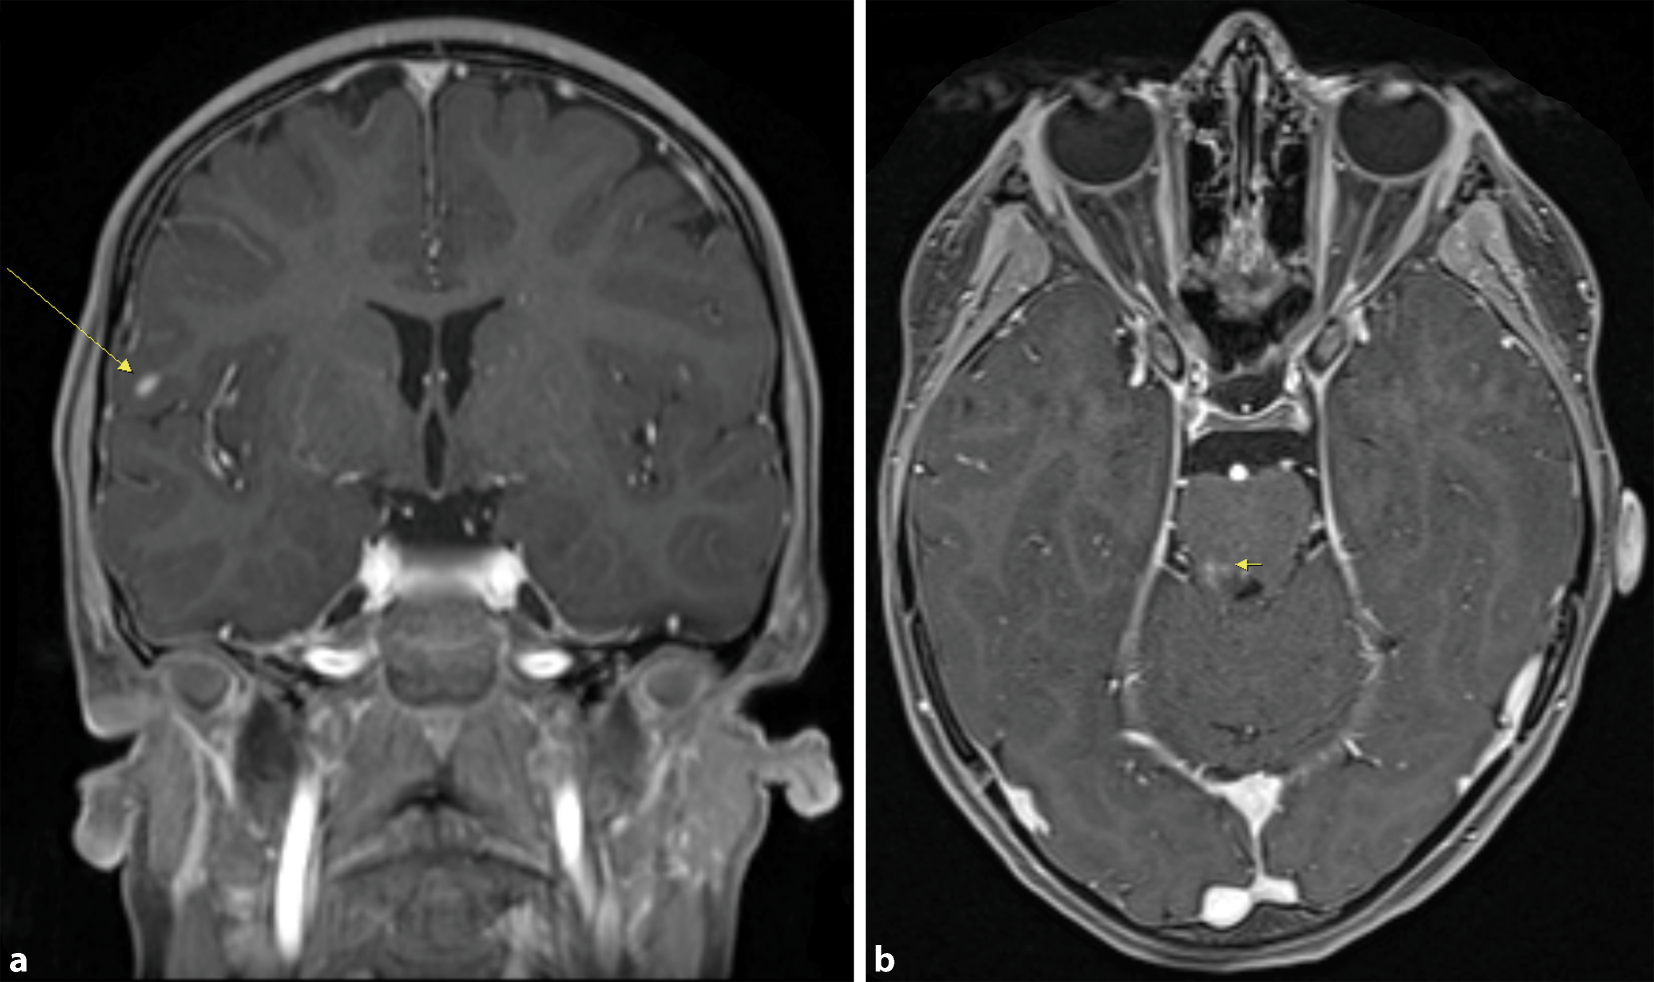

In der kraniellen MR-Tomographie ließen sich 10 periventrikuläre, 12 juxtakortikale sowie eine infratentorielle T2-hyperintense Läsion abgrenzen (Abb. 1). Davon zeigten 2 Läsionen eine Kontrastmittelanreicherung (Abb. 2). Die MRT-Untersuchung des Spinalkanals war unauffällig.

Abb. 1

T2-gewichtete cMRT-Aufnahmen mit hyperintensen Läsionen juxtakortikal und periventrikulär (a) sowie infratentoriell (b)

Präsentation einer besonderes interessanten Patientengeschichte eines 8‑jährigen Mädchens mit plötzlich aufgetretenem partiellen neurologischen Ausfall des III. Hirnnervs. Der zusätzlich bestehende vertikale Nystagmus deutet auf eine über das Kerngebiet des N. oculomotorius hinausgehende, mesenzephale Affektion (Abb. 2). Wegen des erstmaligen Auftretens der Symptome wurde u. a. an eine akute Infektion und an eine akute disseminierte Enzephalomyelitis (ADEM) gedacht. Gegen Letztere spricht das Fehlen eines enzephalopathischen Geschehens. In der MR-Tomographie wurden entsprechend den revidierten McDonald-Kriterien die räumliche Dissemination (T2-hyperintense Läsionen in mindestens 2 der 4 typischen Regionen) und die zeitliche Dissemination (gleichzeitige Präsenz von Kontrastmittel-(Gadolinium)-aufnehmenden und Nicht-Kontrastmittel-(Gadolinium)-aufnehmenden Läsionen) nachgewiesen [1, 2]. Die zeitliche Dissemination wurde ferner durch den Nachweis oligoklonaler Banden bestätigt [2]. Somit sind die bildmorphologischen, klinischen und Liquorbefunde eindeutig mit der Diagnose multiple Sklerose vereinbar.